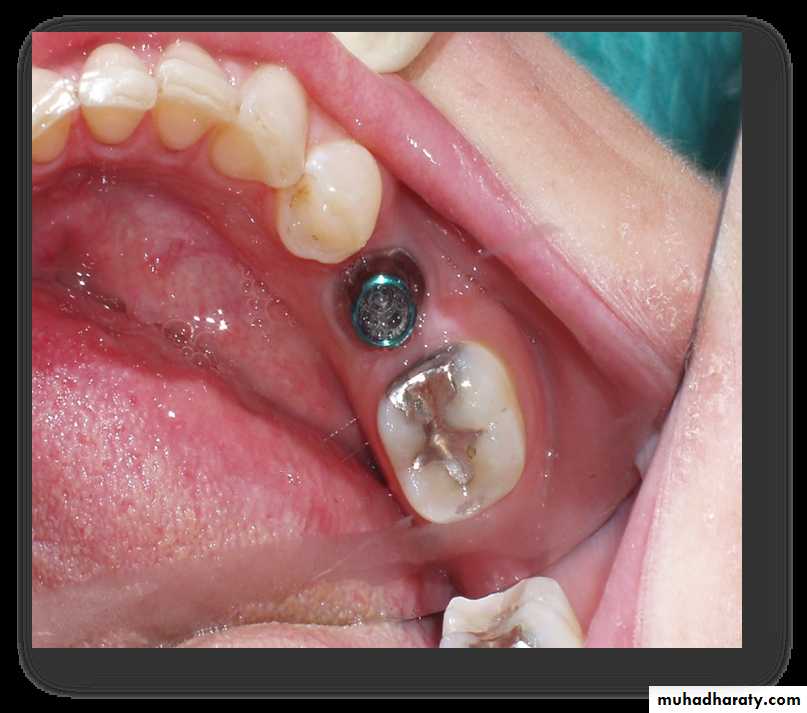

Titanium Mucosal Implants

Epiosteal / Subperiosteal Implants

They placed directly beneath the periosteum overliying the bony cortex (not anchored inside the bone)Receive primary bone support by resting on it.

• Usually indicated in a severely resorbed, completely edentulous mandible which does not offer enough bone height to accommodate root form implants as anchoring devices.